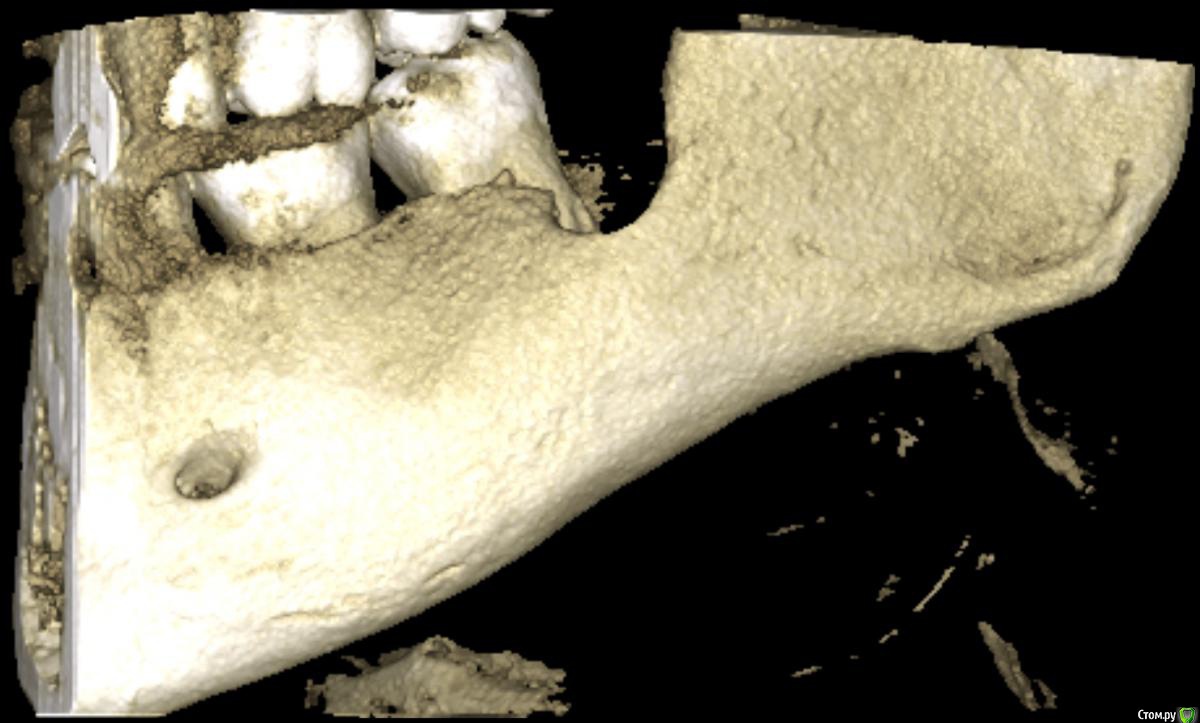

medbratec Опубликовано 12 октября, 2016 Автор Поделиться Опубликовано 12 октября, 2016 Был на консультации в частной клинике.Вердикт - семерку лучше пока не трогать, ее чувствительность обусловлена оголенными корнями. Проводить ревизию лунки, доставать осколок вежливо отказались, и отправляют с этим в челюстно-лицевую.Посоветовали сделать клкт для прояснения картины. Я сделал, однако повторную консультацию пришлось отложить. Не знаю как оттуда вытащить картинки. Если кому будет не лень, то оставлю ссылку на скачивание образа диска. (600мб)Рентгенолог сказал, что осколок в мягких тканях, причем с внутренней стороны, также обнаружилась кариозная полость в месте соприкосновения 7-го и 6-го зуба. Ссылка на комментарий

medbratec Опубликовано 13 октября, 2016 Автор Поделиться Опубликовано 13 октября, 2016 Я вас прекрасно понимаю. Был бы специалистом, то так сразу и сделал. Просто не знаю, что конкретно и под каким углом показывать. Сделал несколько скриншотов. Напишите, если они окажутся не слишком информативны. Ссылка на комментарий

medbratec Опубликовано 13 октября, 2016 Автор Поделиться Опубликовано 13 октября, 2016 Ссылка на комментарий

IvanK Опубликовано 14 октября, 2016 Поделиться Опубликовано 14 октября, 2016 скорее всего , это пломбировочный материал, лежит он не в костной ткани, а в мягких тканях, если не беспокоит, то можно не трогать 1 Ссылка на комментарий

red_butler Опубликовано 17 октября, 2016 Поделиться Опубликовано 17 октября, 2016 если это пломбировочный материал то на снимках "до" он должен быть, но я вижу там что то металлическое 2 Ссылка на комментарий

kramer Опубликовано 22 октября, 2016 Поделиться Опубликовано 22 октября, 2016 если это пломбировочный материал то на снимках "до" он должен быть, но я вижу там что то металлическоеЧисто по снимку похоже на кончик твердосплавного бора. ИМХО. Ссылка на комментарий